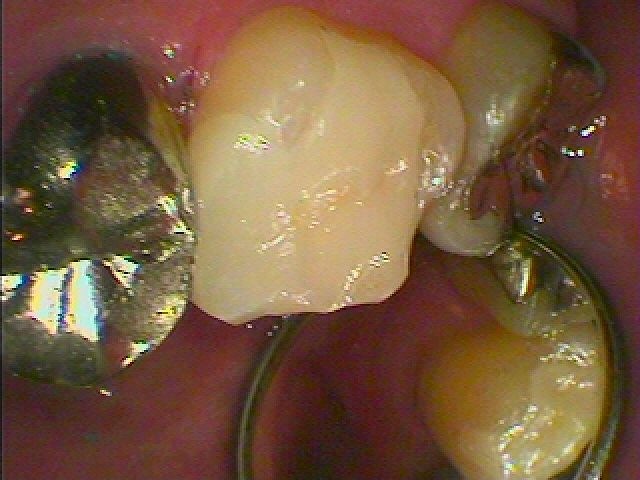

セレックセラミックにて審美的に綺麗に修復しています

汚れも付きにくく現代病であるアレルギーも無く良いマテリアルになります

本来の歯のようにきれいに仕上がりました